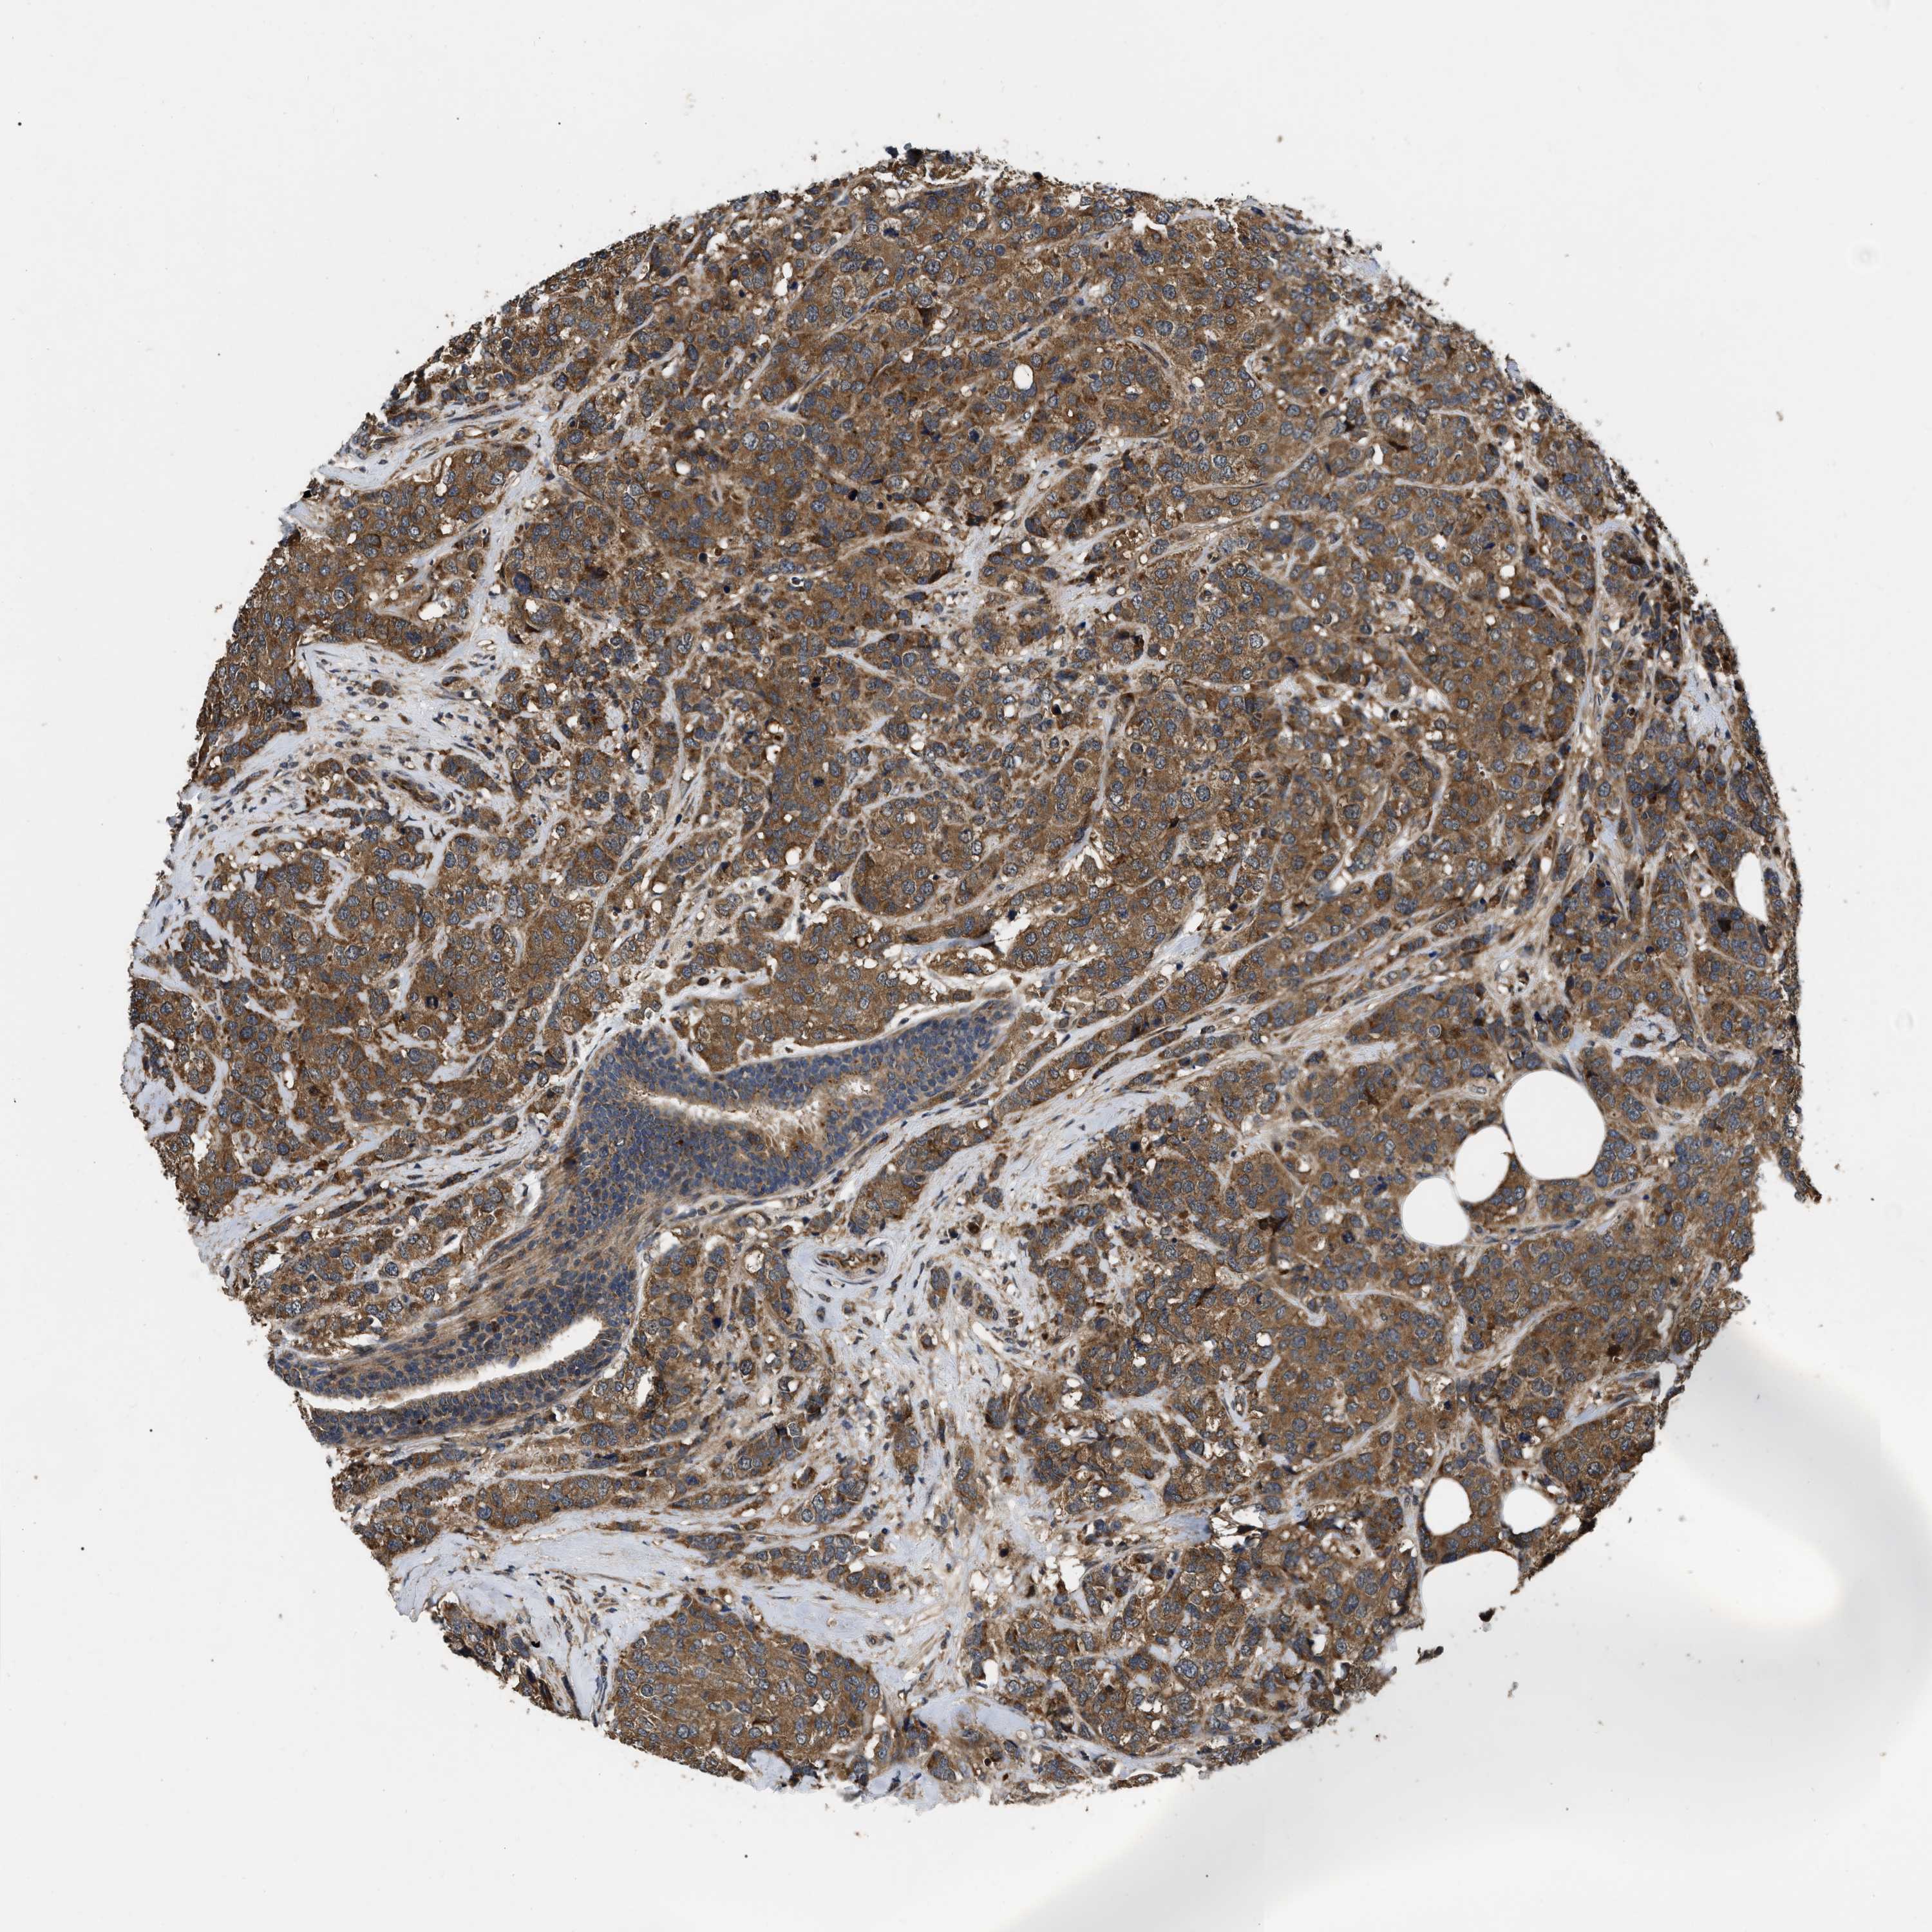

CANCER BREAST CANCER Show tissue menu

BRCA TCGA BRCA VALIDATION PROTEIN EXPRESSION